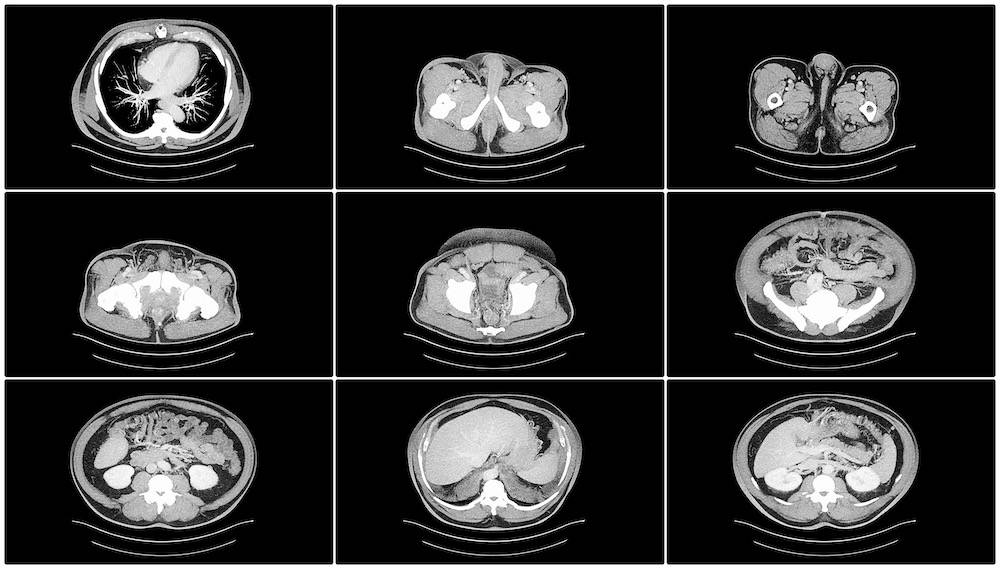

CT oder MRT bauchraum

Sowohl MRT- als auch CT-Scans ermöglichen es den Ärzten, das Innere des Unterleibs eines Patienten zu sehen, so dass sie die Ursache für die Probleme finden können. Beide haben Vor- und Nachteile, so dass man sich individuell informieren sollte, bevor man sich für die eine oder die andere Methode entscheidet. Sie können auch mit einem Arzt sprechen, der ihnen weitere Informationen über ihre Möglichkeiten geben kann.

Die MRT wird von den Patienten vor allem deshalb bevorzugt, weil sie im Gegensatz zu CT-Untersuchungen keine Strahlenbelastung mit sich bringt. Die Bilder, die die MRT liefert, sind auch viel klarer als die von Röntgenstrahlen, was es dem Arzt ermöglicht, eine korrekte Diagnose zu stellen und einen effizienten Behandlungsplan zu erstellen.

Es gibt jedoch auch Situationen, in denen Ärzte eine CT-Untersuchung anstelle einer MRT-Untersuchung des Bauchraums empfehlen können. Menschen mit implantierten medizinischen Geräten können unter Umständen nicht an einer MRT-Untersuchung teilnehmen, weshalb in ihrer Situation die CT-Untersuchung bevorzugt wird. Eine MRT-Untersuchung dauert auch länger als eine CT-Untersuchung. Wenn Patienten also schnell etwas herausfinden müssen, werden sie sich wahrscheinlich für die zweite Option entscheiden. (5)